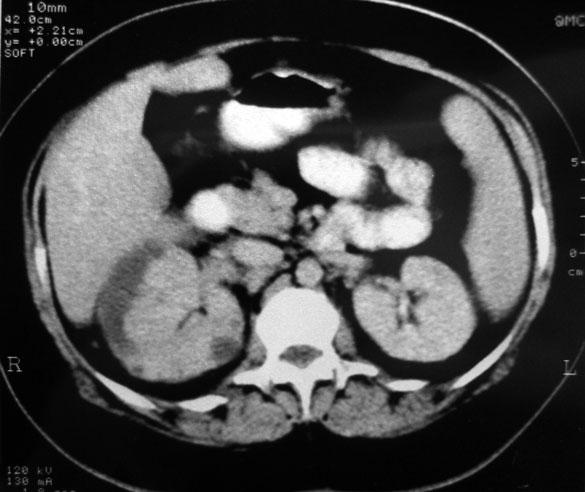

Chronological Photo-sequence

of the case progression

-After 2 months of presentation and treatment: